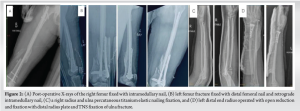

Upon arrival at our center, the patient was found hypotensive (90/60 mmg) and tachypnoeic (Respiratory rate – 31/min). She was stabilized in the emergency room and transferred to the Intensive Care Unit (ICU), where additional ventilatory support with bilevel-positive airway pressure (BiPAP) was provided in accordance to sustained hypotension and increasing oxygen requirements. Comprehensive evaluations, ranging across echocardiography to CT scans, revealed mild global left ventricular hypokinesia and multiple rib fractures, amongst add vcdsitional findings. As the patient was able to achieve hemodynamic stability after 2 days in the ICU following resuscitation, orthopaedic interventions were provided based on principles of EDF. This included intramedullary nailing of the right femur, and distal femoral nailing alongside plating by lateral condylar locking plate over the left femur. Open reduction with internal fixation of the left wrist was performed through distal radius plating and titanium elastic nail (TENS) fixation of the ulna, and percutaneous TENS fixation contralaterally of the left radius and ulna(Fig. 2). Fixation of the right acetabulum was undertaken by a percutaneous antegrade posterior column screw, on June 20th and 23rd of 2023. Subsequently, complications of pleural effusion and subcutaneous emphysema set in, which were managed by re-insertion of ICD tube along with appropriate medical care.